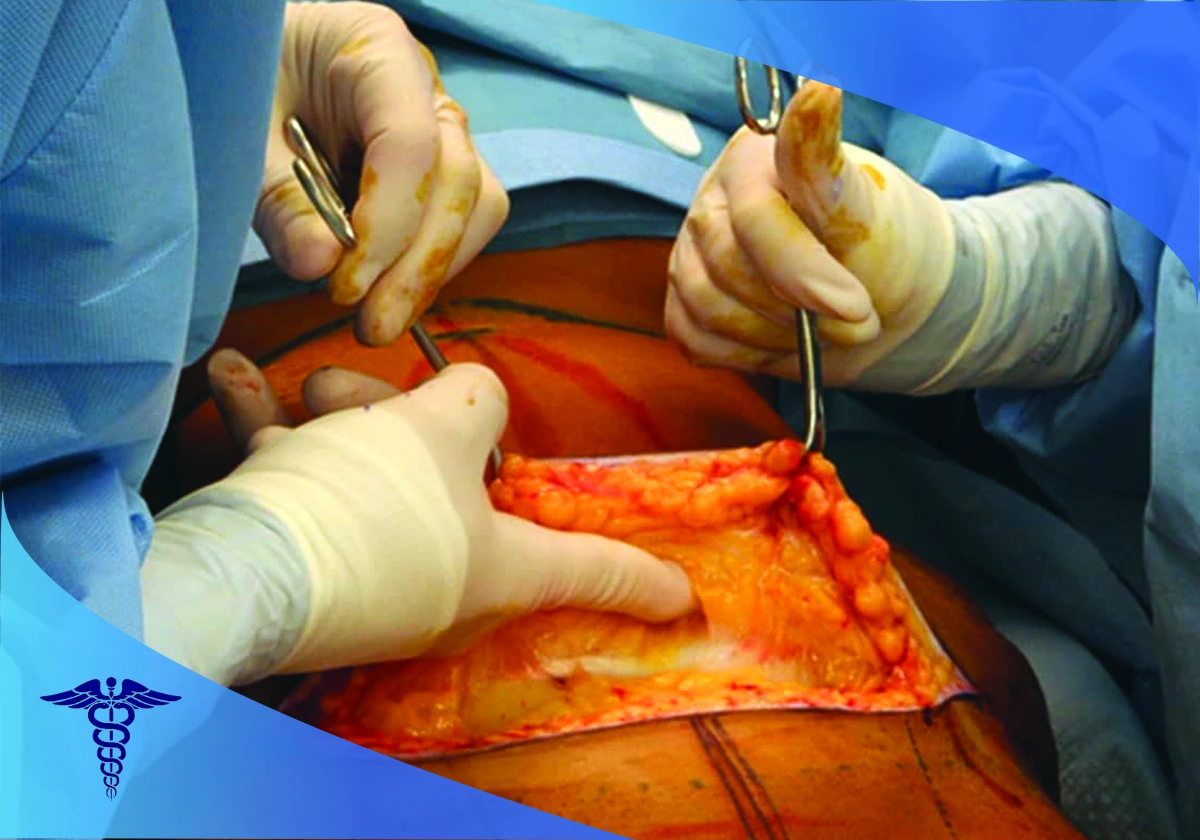

برداشت پوست و چربی اضافه

در این مرحله دسترسی به چربی های اضافی دور شکم ایجاد شده و این چربیها خارج می شوند. همچنین بخشی از پوست شکم که خاصیت ارتجاعی نداشته و شل و آویزان شده است، برداشته می شود. عضلات شکم نیز که حالت شل شدگی پیدا کرده اند به یکدیگر نزدیک شده و سفت می شوند.

بخیه و پانسمان

پس از برداشت چربی و پوست اضافی، پوست باقیمانده کشیده شده و نواحی برش داده شده بخیه و سپس پانسمان می شوند. مهارت پزشک جراح در این مرحله در کاهش جای زخم و بخیه ها و در نهایت زیبایی شکم بسیار تعیین کننده و کارساز است.